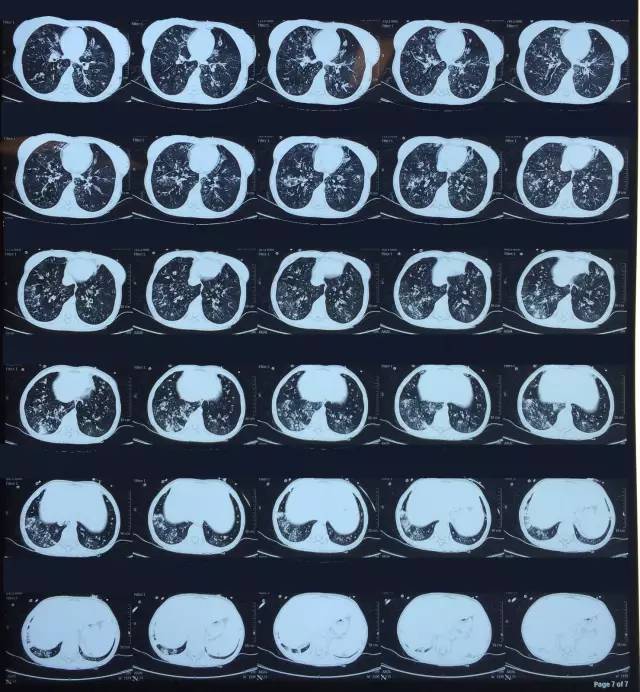

肺CT見(jiàn)下圖

該患者肺部影像學(xué)表現(xiàn)為明顯的支氣管擴(kuò)張,同時(shí)伴有彌漫的滲出斑片影,考慮合并感染,細(xì)菌學(xué)培養(yǎng)提示為綠膿桿菌,結(jié)合藥敏結(jié)果給予頭孢他啶+阿米卡星抗感染,患者存在II型呼吸衰竭予氣管插管機(jī)械通氣支持,加強(qiáng)體位引流排痰,治療18天,患者情況好轉(zhuǎn)出院。